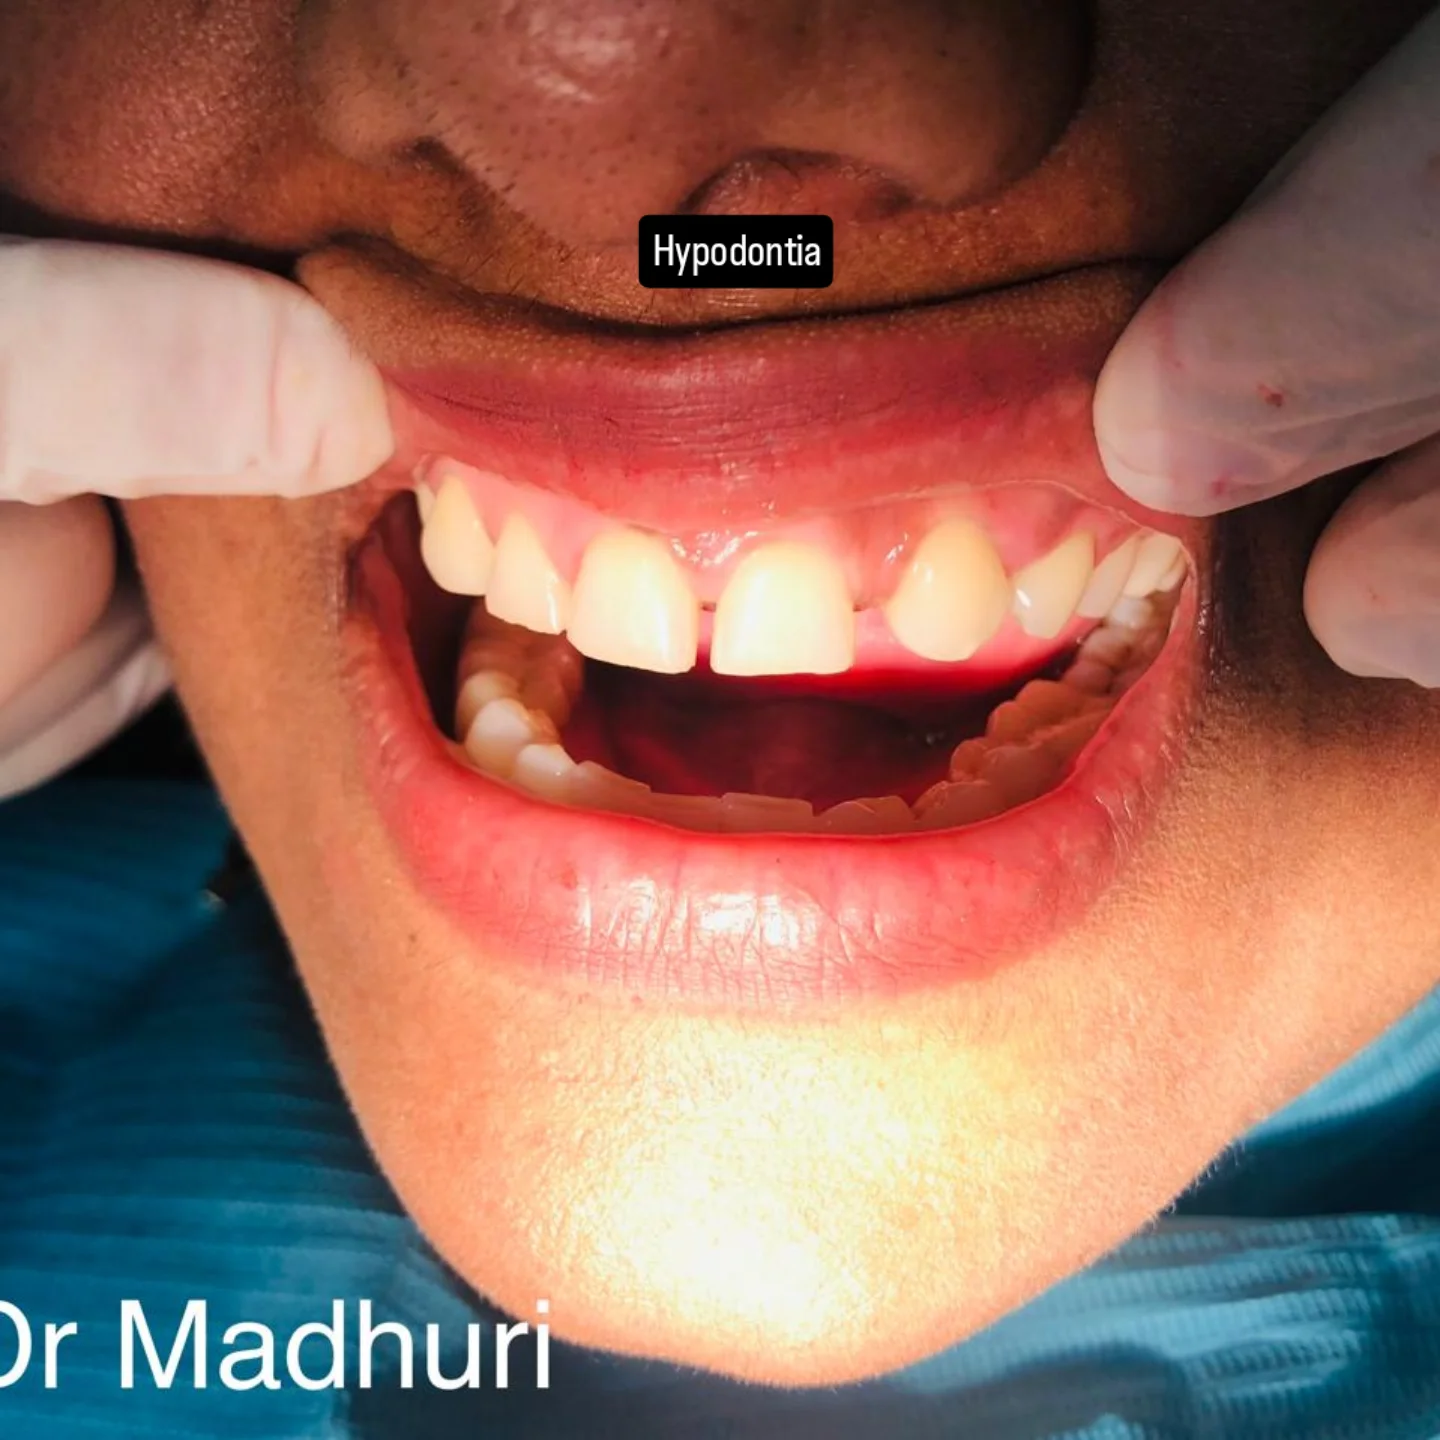

Explore Our Clinical Dental Gallery

Welcome to our official treatment gallery, showcasing the real results, smile transformations, and advanced dental care delivered by Dr. Madhuri. We believe that a picture is worth a thousand words when it comes to the art and precision of modern dentistry. Review our comprehensive visual portfolio below to see how our dedicated care helps patients achieve healthy, beautiful, and confident smiles.